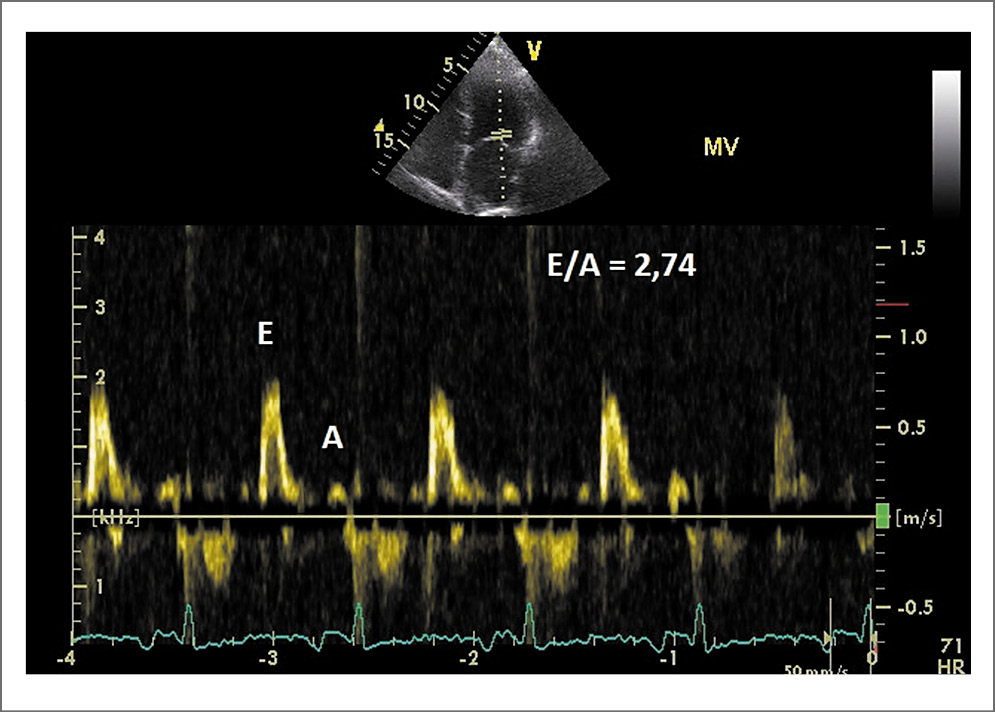

Рис. 3. Допплерограмма трансмитрального кровотока (Е – скорость раннего наполнения ЛЖ; А – скорость наполнения ЛЖ в фазу систолы предсердий). Паттерн свидетельствует о рестриктивном типе наполнения ЛЖ (Е/А>2), т.е. повышено давление в ЛП

- выраженная диастолическая дисфункция ЛЖ: рестриктивный тип наполнения ЛЖ (повышено конечно-диастолическое давление ЛЖ), Е/e’=35; максимальная скорость трикуспидальной регургитации 3,2 м/с (см. рис. 3, 4).